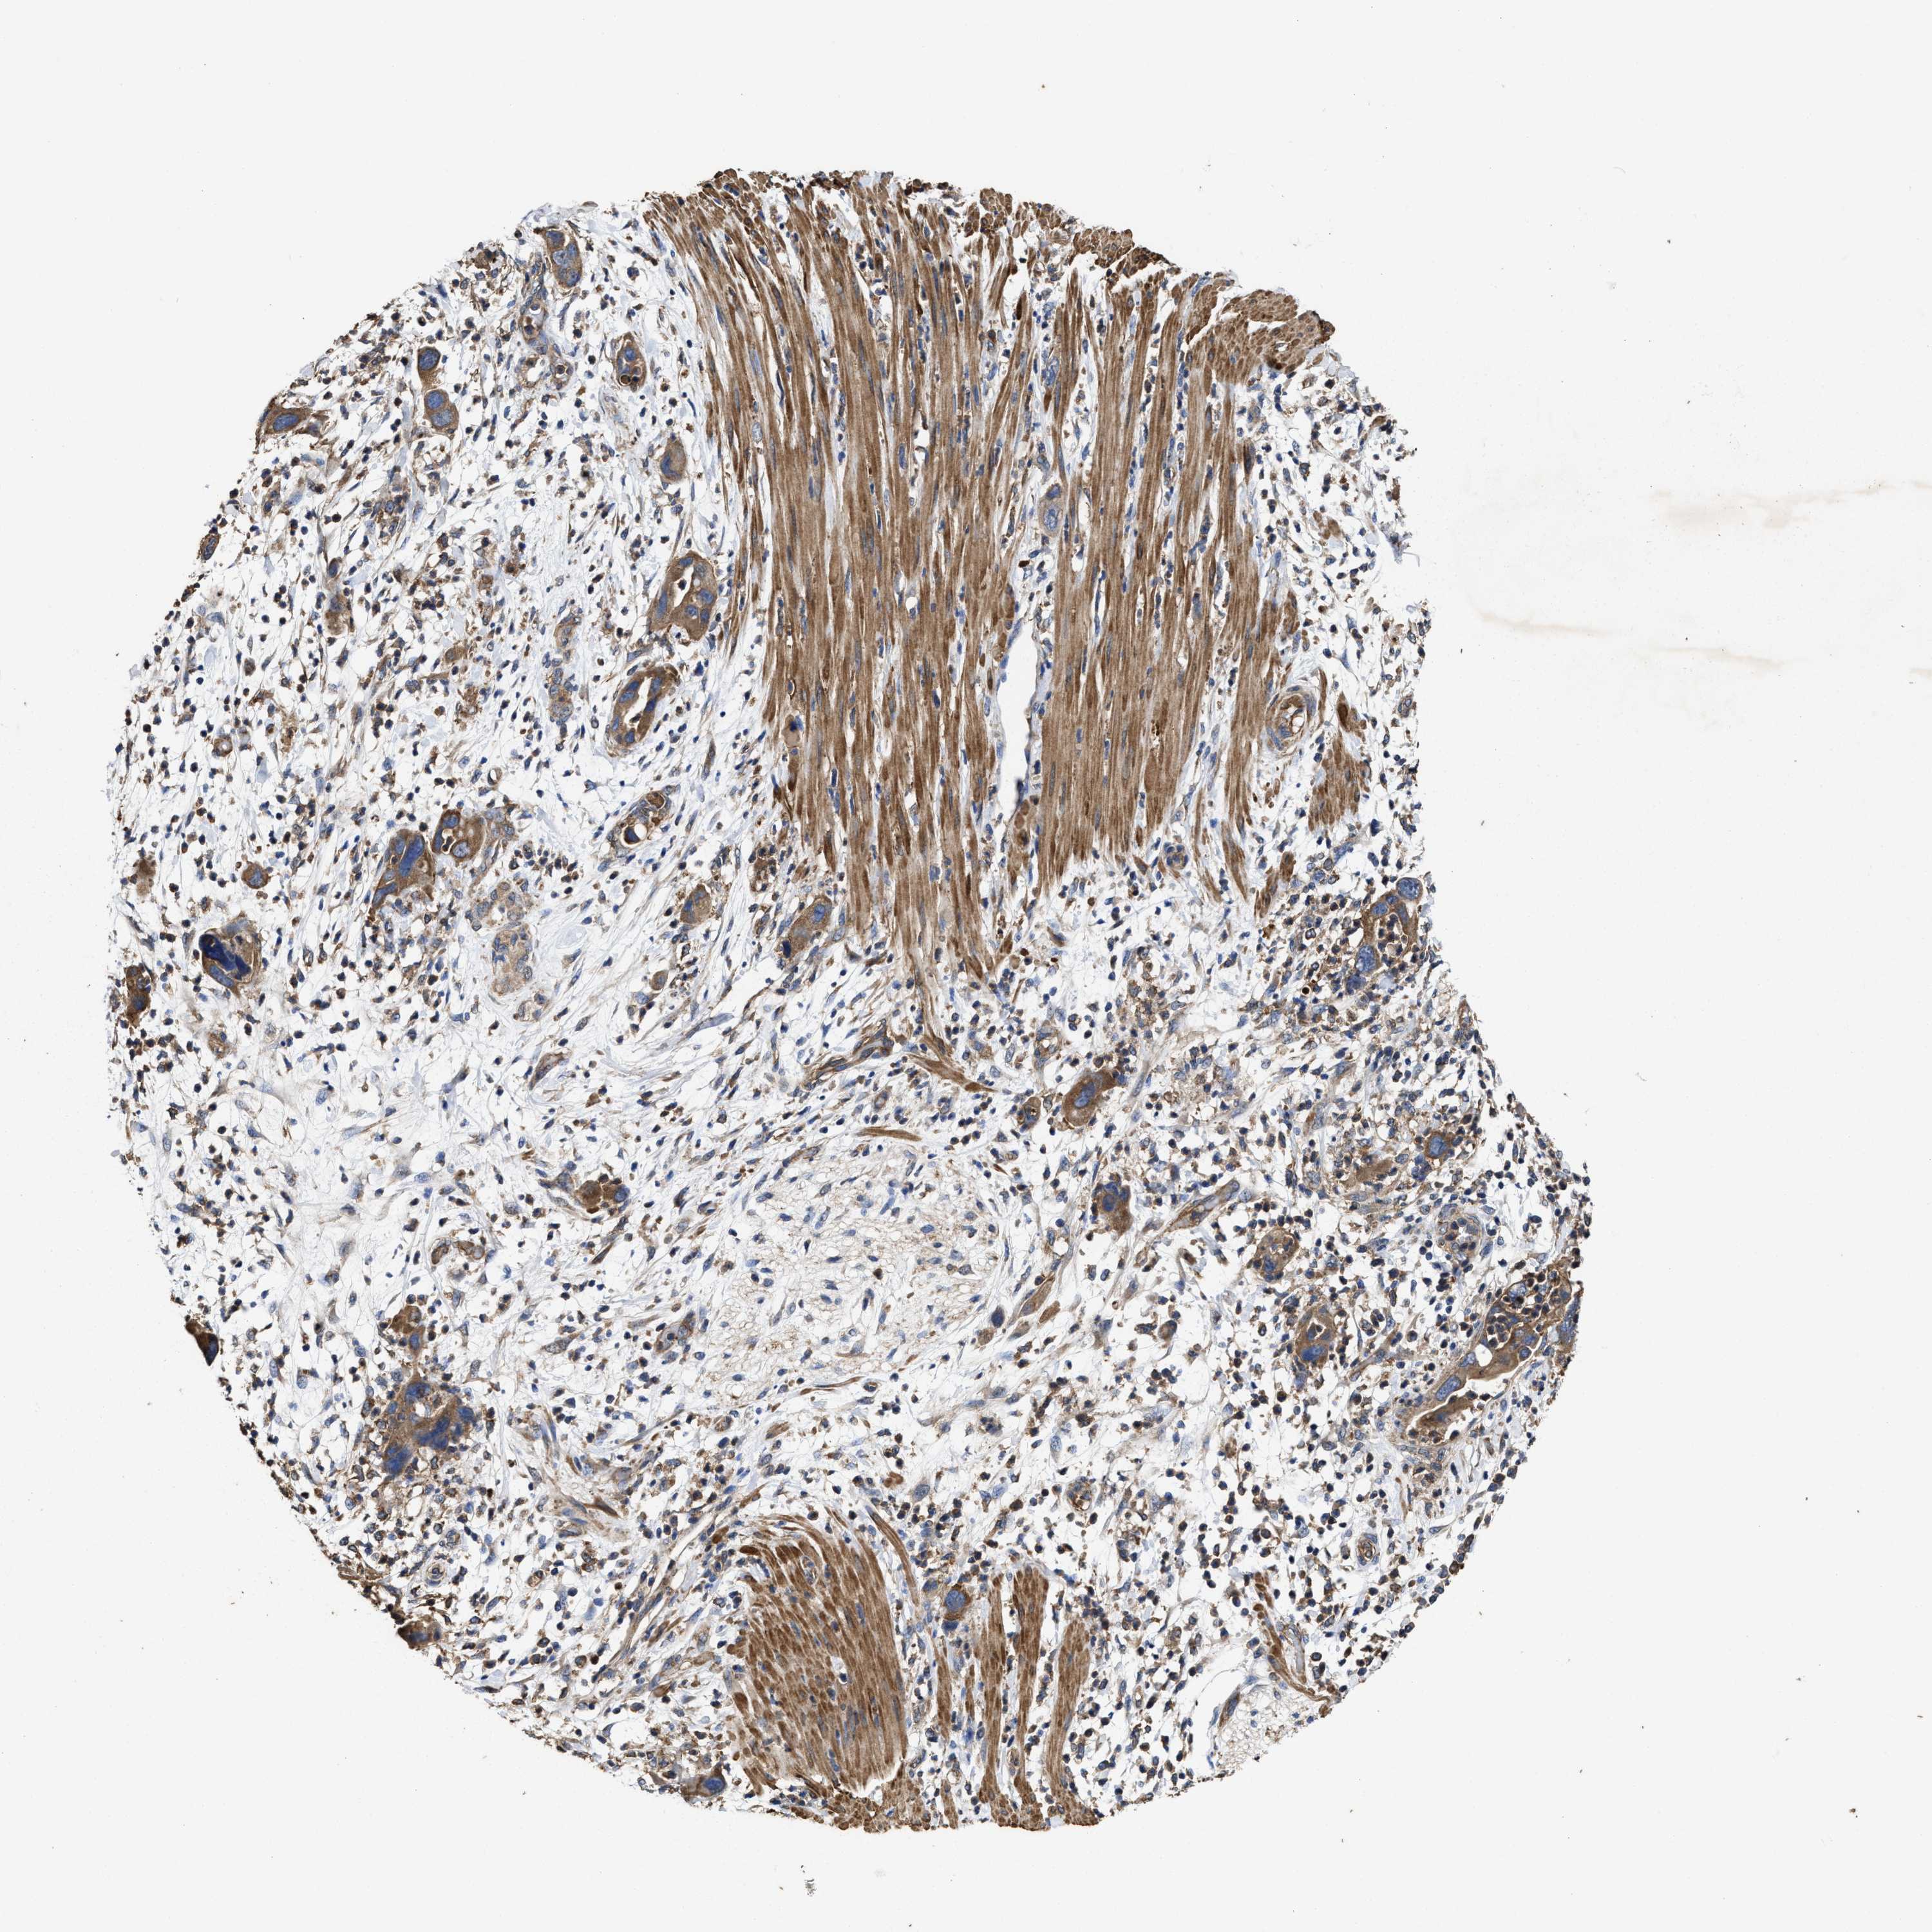

PANCREATIC CANCER - Protein expressioni

A mouse-over function shows sample information and annotation data. Click on an image to view it in a full screen mode. Samples can be filtered based on level of antibody staining by selecting one or several of the following categories: high, medium, low and not detected. The assay and annotation is described here.

Note that samples used for immunohistochemistry by the Human Protein Atlas do not correspond to samples in the TCGA dataset.

Antibody stainingi

Antibody staining in the annotated cell types in the current human tissue is reported as not detected, low, medium, or high, based on conventional immunohistochemistry profiling in selected tissues. This score is based on the combination of the staining intensity and fraction of stained cells.

Each image is clickable and will lead to virtual microscopy that enables deeper exploration of all samples and also displays staining intensity scores, fraction scores and subcellular localization as well as patient and tissue information for each sample.

Antibody HPA020872

Staining

High

Medium

Low

Not detected

Intensity

Strong

Moderate

Weak

Negative

Quantity

>75%

75%-25%

<25%

None

Location

Nuclear

Cytoplasmic/membranous

Cytoplasmic/membranous,nuclear

Adenocarcinoma, NOS